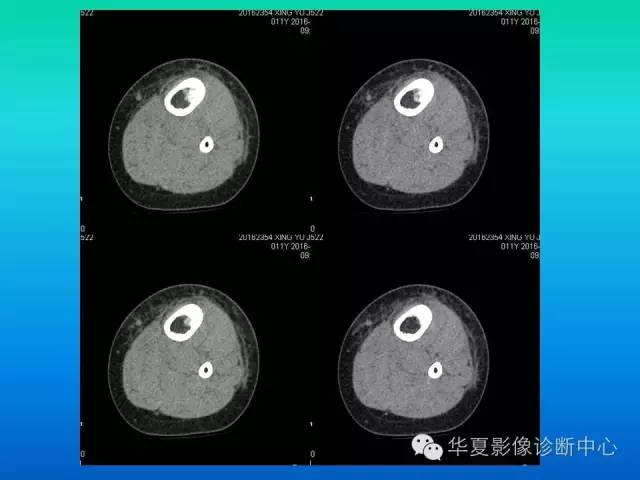

【病例】胫骨非骨化性纤维瘤1例CT影像表现

患者:男,11岁,腿疼

病理结果【非骨化性纤维瘤】

CT:

1)病灶呈圆形或卵圆形囊状低密度区,有分房时形似蜂窝状或皂泡状。

2)边界清晰,有线形骨硬化带环绕,局部骨皮质稍膨胀变薄,但很少突向骨外。

3)病灶常位于干骺端,距骨骺线3~4厘米处,呈偏心性,多在皮质下。